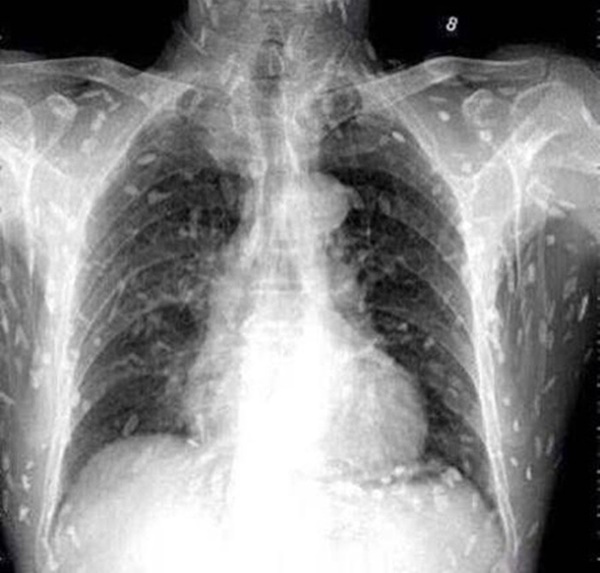

Tuy nhiên, do bệnh tình đã bước sang giai đoạn nghiêm trọng nên người đàn ông tiếp tục được chuyển tới Bệnh viện Nhân dân số 8 ở Quảng Châu để điều trị. Kết quả chụp X-quang cho thấy, những đốm trắng nhỏ xuất hiện lấm chấm khắp cơ thể chính là sán.

Những chấm trắng xuất hiện trên hình chụp X-quang là sán.